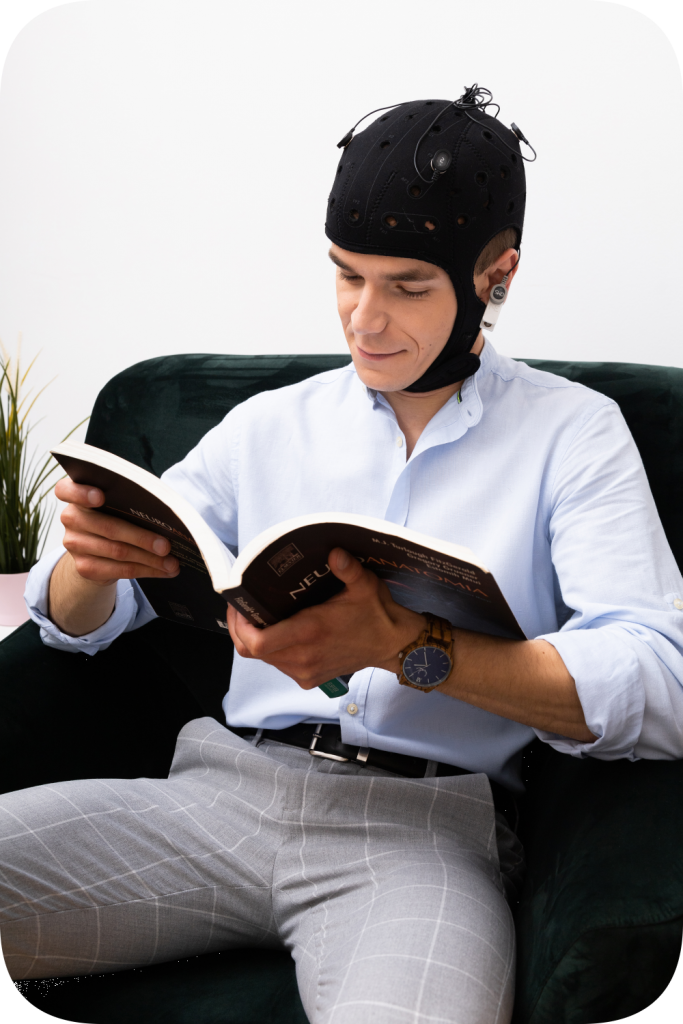

Jest to nieinwazyjna bezpieczna stymulacja, najczęściej występującymi efektami nie pożądanymi jest zaczerwienienie skóry, swędzenie bądź pieczenie podczas stymulacji, które po około 4-5 minutach ustępuje. Zaawansowana technologicznie terapia schorzeń o podłożu neurologicznym, która charakteryzuje się bardzo wysokim stopniem bezpieczeństwa oraz wysoką skutecznością, potwierdzoną licznymi badaniami klinicznymi. Czy nieinwazyjna stymulacja przezczaszkowa pomaga? Metodę tę stosuje się z powodzeniem u osób, u których tradycyjne metody terapii okazały się niewystarczające lub nieskuteczne. Może być ona stosowana także wspomagająco, przy równoczesnym korzystaniu z innych form terapii i leczenia. Przezczaszkowa stymulacja prądem to metoda powodująca zmiany pobudliwości w korze mózgowej dzięki wykorzystaniu słabego, bezpiecznego dla organizmu prądu o natężeniu w przedziale od 0 do 2 mA dla jednej elektrody. Terapia daje zauważalne rezultaty zmierzające do poprawy komfortu życia pacjenta poprzez zmiany pracy mózgu, redukcję bólu oraz wspieranie i poprawę procesów poznawczych (pamięci, myślenia, uwagi, mowy, zdolności percepcyjnych itp.). Do stymulacji wykorzystywane jest bezprzewodowe urządzenie mocowane na czepku wraz z elektrodami (tak jak na prezentowanym zdjęciu).